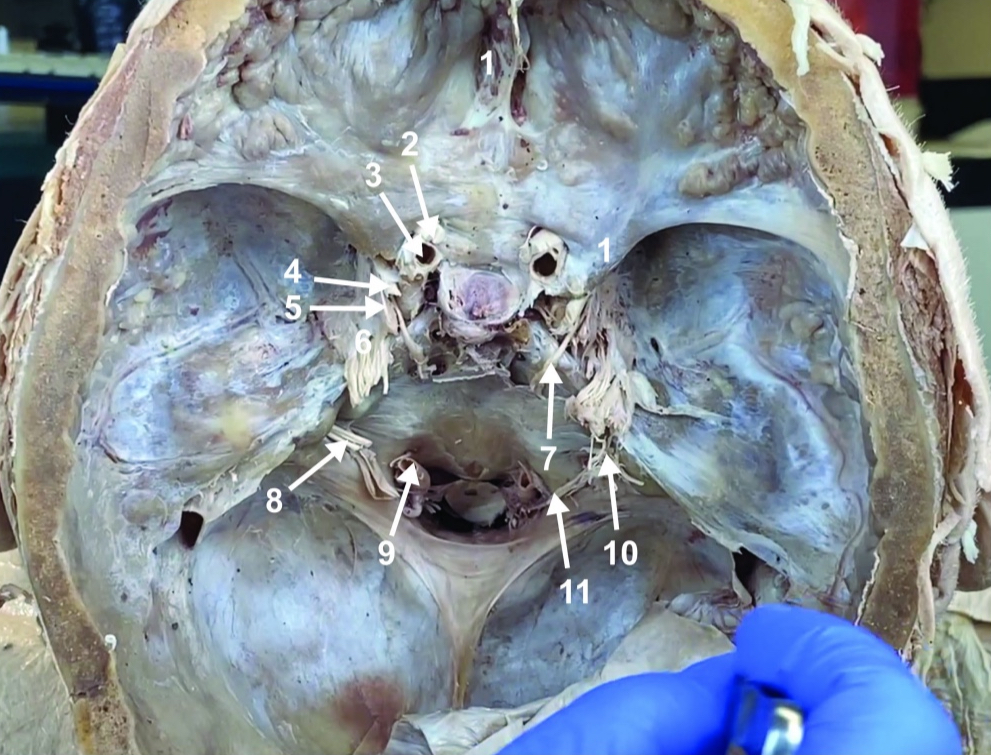

Foramen magnum

Foramen ovale

Foramen spinosum

Cribiform plate

Optic n. (CN II)

Internal carotid a. (ICA)

Occulomotor n. (CN III)

Trochlear n. (CN IV)

Trigeminal n. (CN V)

Abducent n. (CN VI)

Facial and vestibulocochlear n. (CN VII and VIII)

Vertebral a.

Glossopharyngeal and vagus n. (CN IX and X)

Root of spinal accessory n. (root of CN XI)

Ophthalmic division of CN V (CN V1)

Maxillary division of CN V (CN V2)

Mandibular division of CN V (CN V3)

Foramen rotundum

Foramen ovale

Trochlear n. (CN IV)

Abducent n. (CN VI)